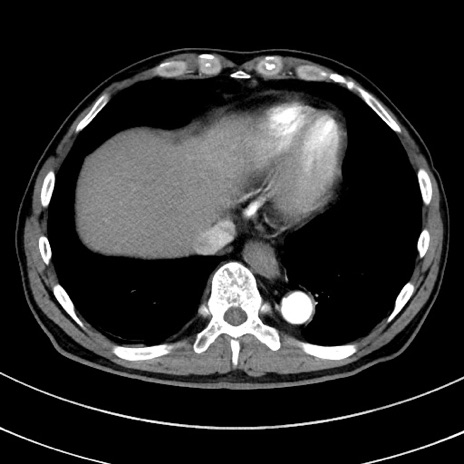

症例8(横断像)

【症例】 60歳代男性

【主訴】 黒色吐物

【現病歴】 4日前から嘔気自覚、2日前の朝食後にも嘔気あり、自分で手で嘔吐反射起こし嘔吐したところ血が混ざっていたため受診。

【既往歴】 5年前汎発性腹膜炎を伴う急性虫垂炎で手術、高血圧、前立腺肥大症、高脂血症

【身体所見】 腹部正中に手術癩痕あり 腹部平坦・軟圧痛なし膨満感あり

【データ】WBC 8400、CRP 4.54